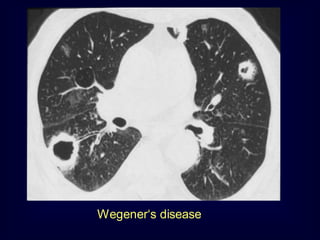

Wegener‘s disease